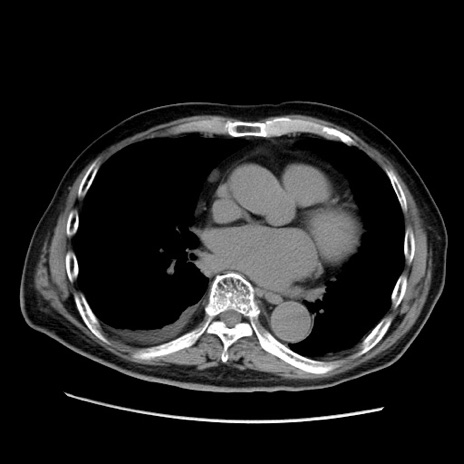

冠状断像